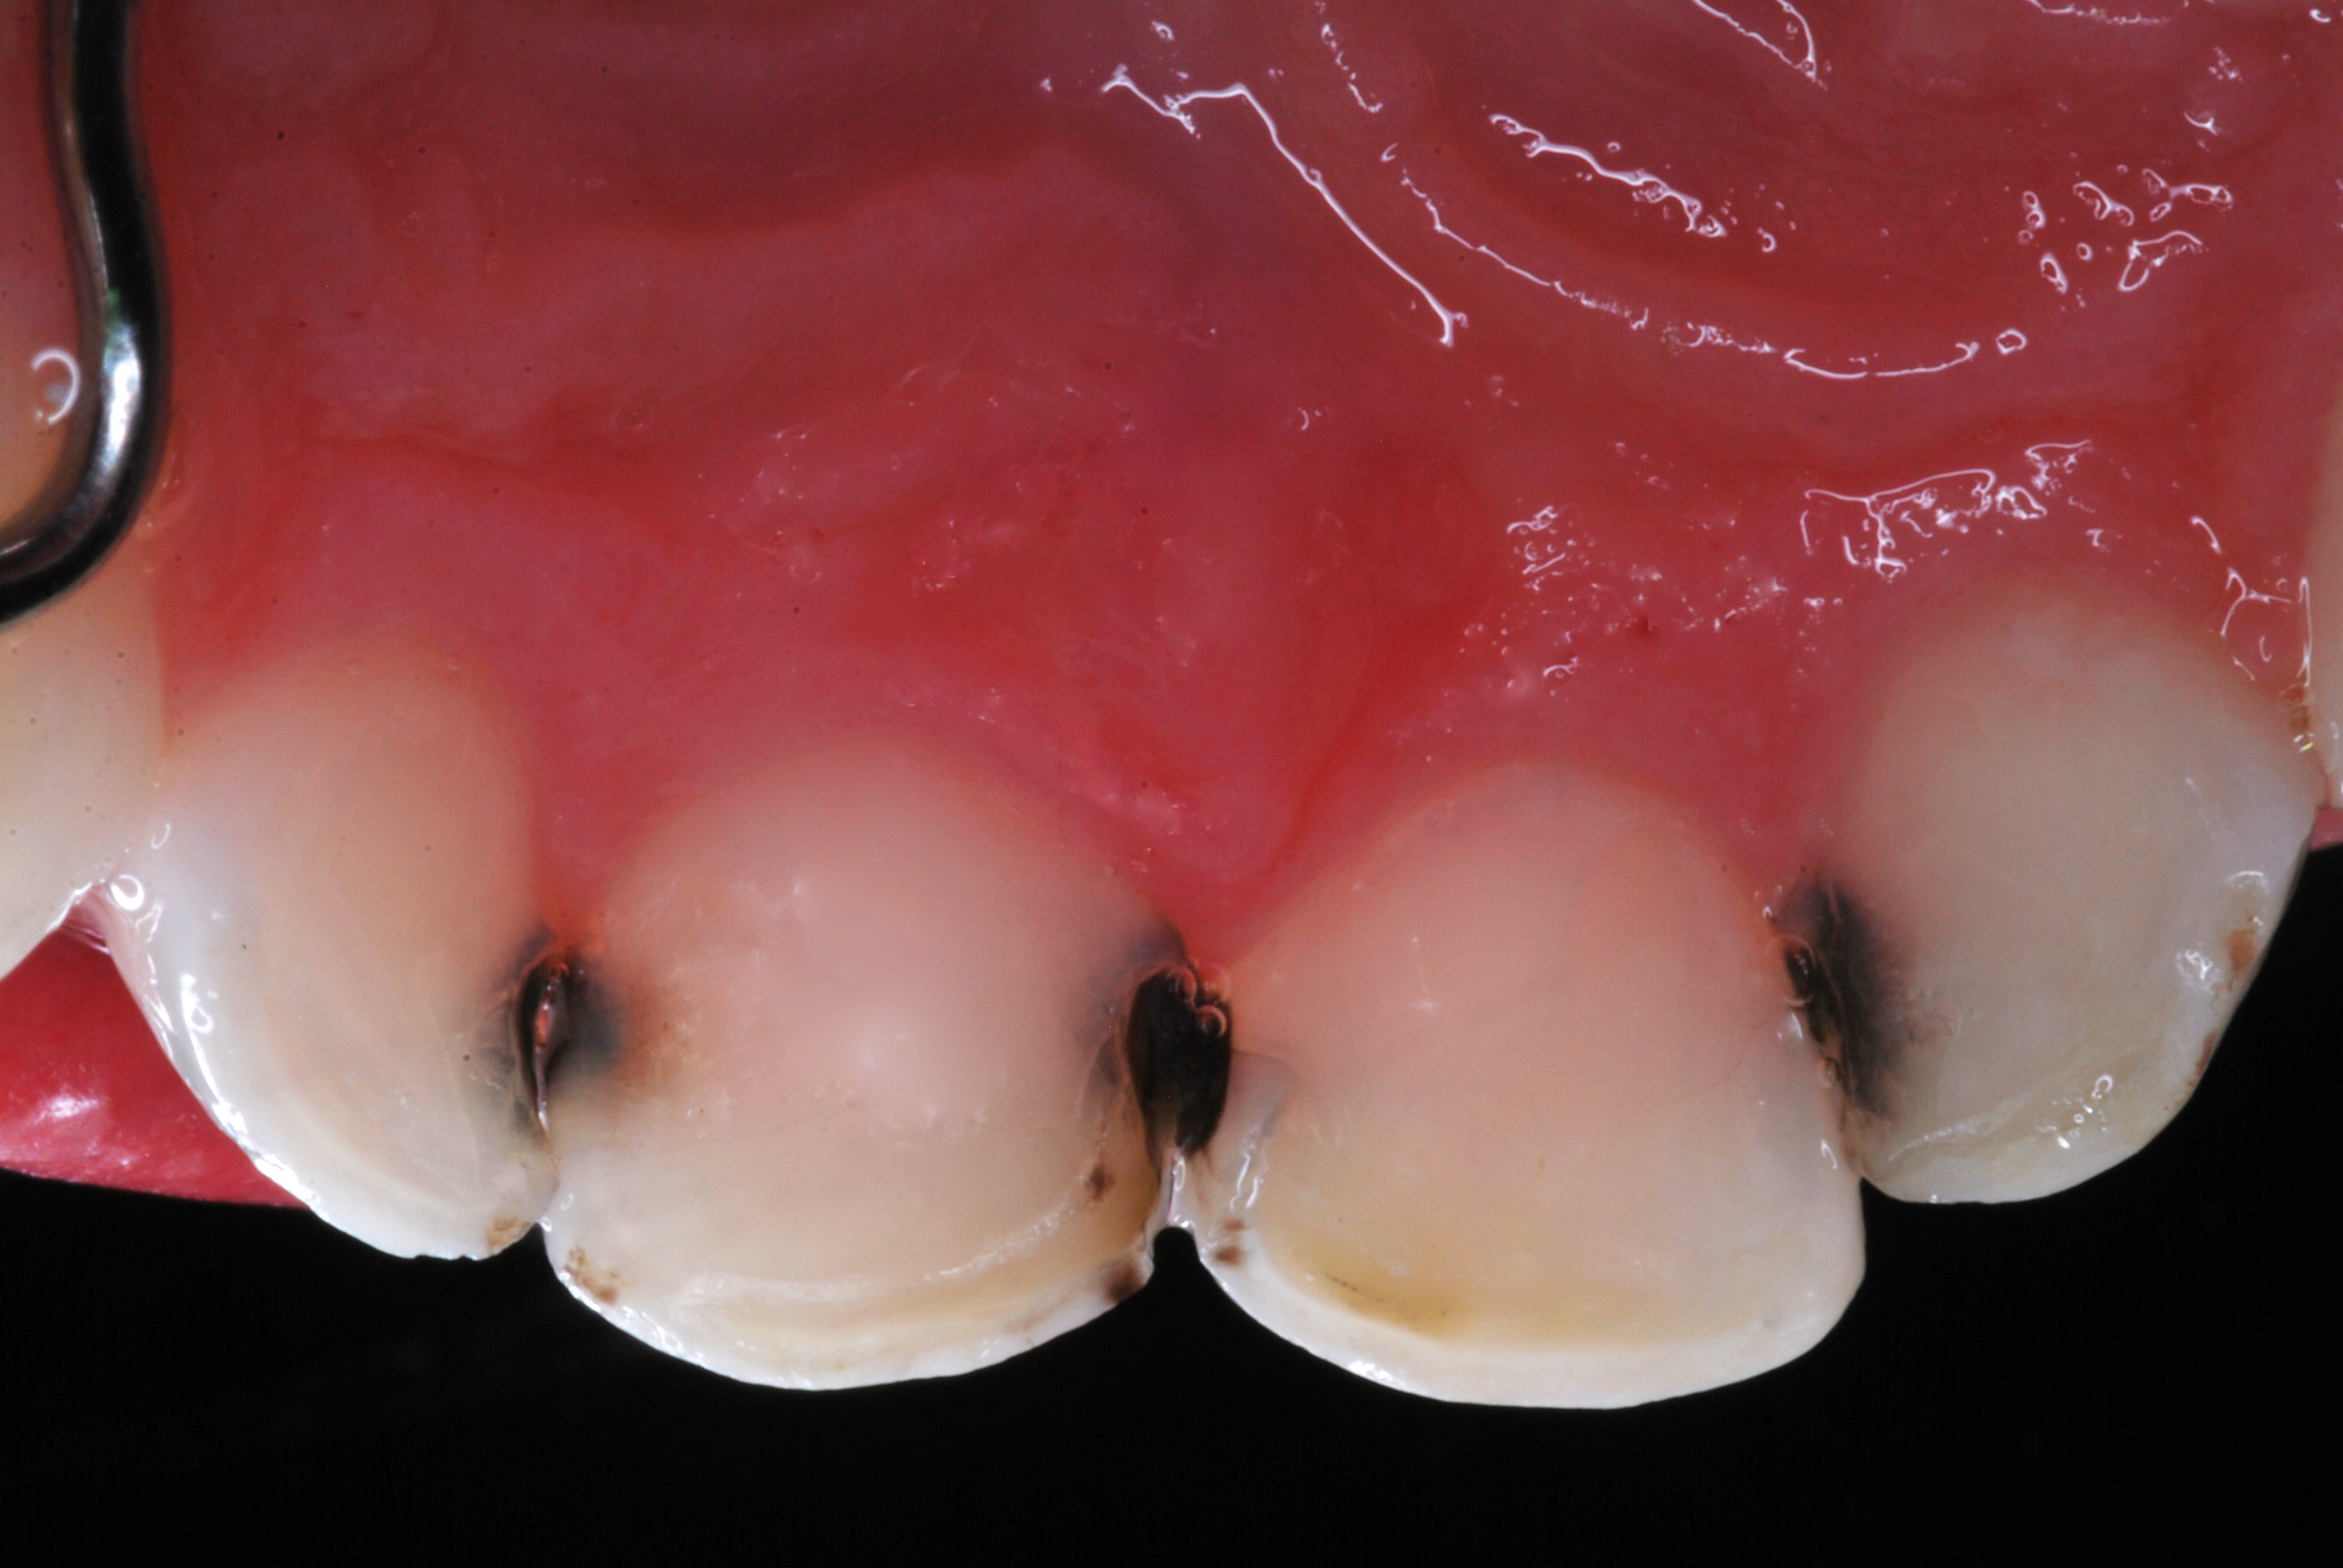

(2.) Lingual and facial maxillary views of 5-year-old patient, 1 year after caries attenuation with SDF. The parents were not concerned about the black staining.

Figure 2

(3.) Lingual and facial maxillary views of 5-year-old patient, 1 year after caries attenuation with SDF. The parents were not concerned about the black staining.

Figure 3